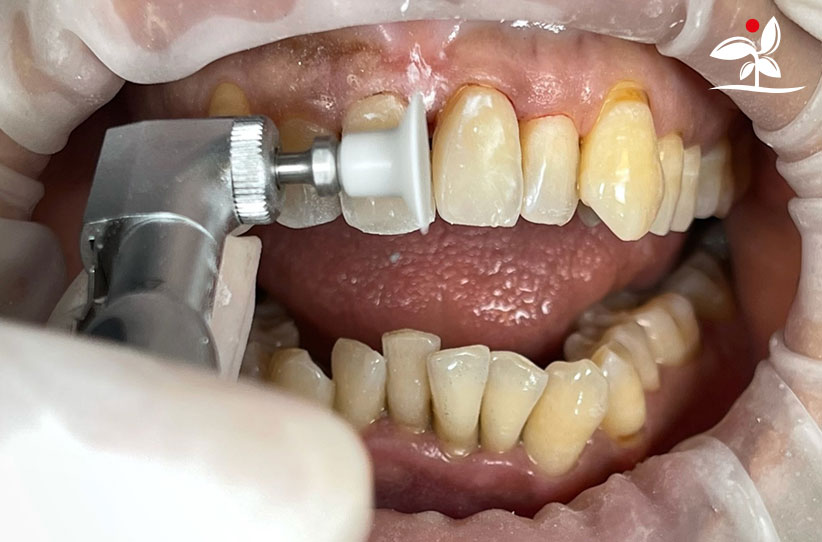

Restoration of Class IV Lesions using Naturomimetic Layering Technique (NLT) and Bioactive Restorative Materials

With the growing awareness about the health, function and aesthetic benefits of preserving natural tooth structure, patients are now globally demanding for aesthetic dentistry with minimally invasive procedures that has a low biological cost. This public demand has encouraged logical clinicians to adopt to the minimally invasive cosmetic dentistry (MiCD) concept and its treatment protocol [1] in their practice. The author has been using MiCD concept and its treatment protocols since 2017, which

include the methods of treatment that are simple, fast, predictable and healthy. In aesthetic restoration, the tooth color restorative materials placement technique is one of the most challenging, confusing and frustrating areas to learn owing to the multiple techniques that have been proposed by many clinicians and replicating such techniques in practice is not always as easy as they are marketed in dentistry. Natural teeth are complex in structure and hard to simulate due distribution of colors through enamel and dentin [2]. Aesthetic restoration strategies should follow proper understanding of defects, right selection of restorative materials along with their proper application, finishing, texturing and polishing [2].